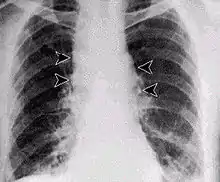

Inhalational anthrax, mediastinal widening

It infects the lymph nodes in the chest first, rather than the lungs themselves, a condition called hemorrhagic mediastinitis, causing bloody fluid to accumulate in the chest cavity, thereby causing shortness of breath. The second (pneumonia) stage occurs when the infection spreads from the lymph nodes to the lungs. Symptoms of the second stage develop suddenly within hours or days after the first stage. Symptoms include high fever, extreme shortness of breath, shock, and rapid death within 48 hours in fatal cases.[28]